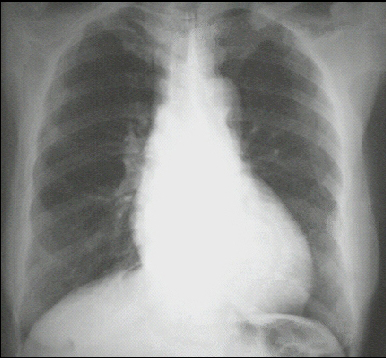

PA view

These chest X rays show left ventricular enlargement and a dilated aorta. The PA view demonstrates cardiomegaly, as evidenced by a cardiothoracic ratio greater than 50%. Note also the increased inferolateral cardiac border that is consistent with left ventricular enlargement due to volume overload. The ascending, transverse, and descending aortic shadows are also prominent. The lateral view shows left ventricular enlargement, as evidenced by posterior displacement of the left ventricular shadow.